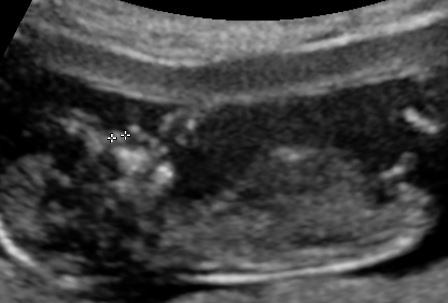

Pls guess girl or boy based on Nubs theory or skull theory?

12 weeks scan.

Heart rate 167